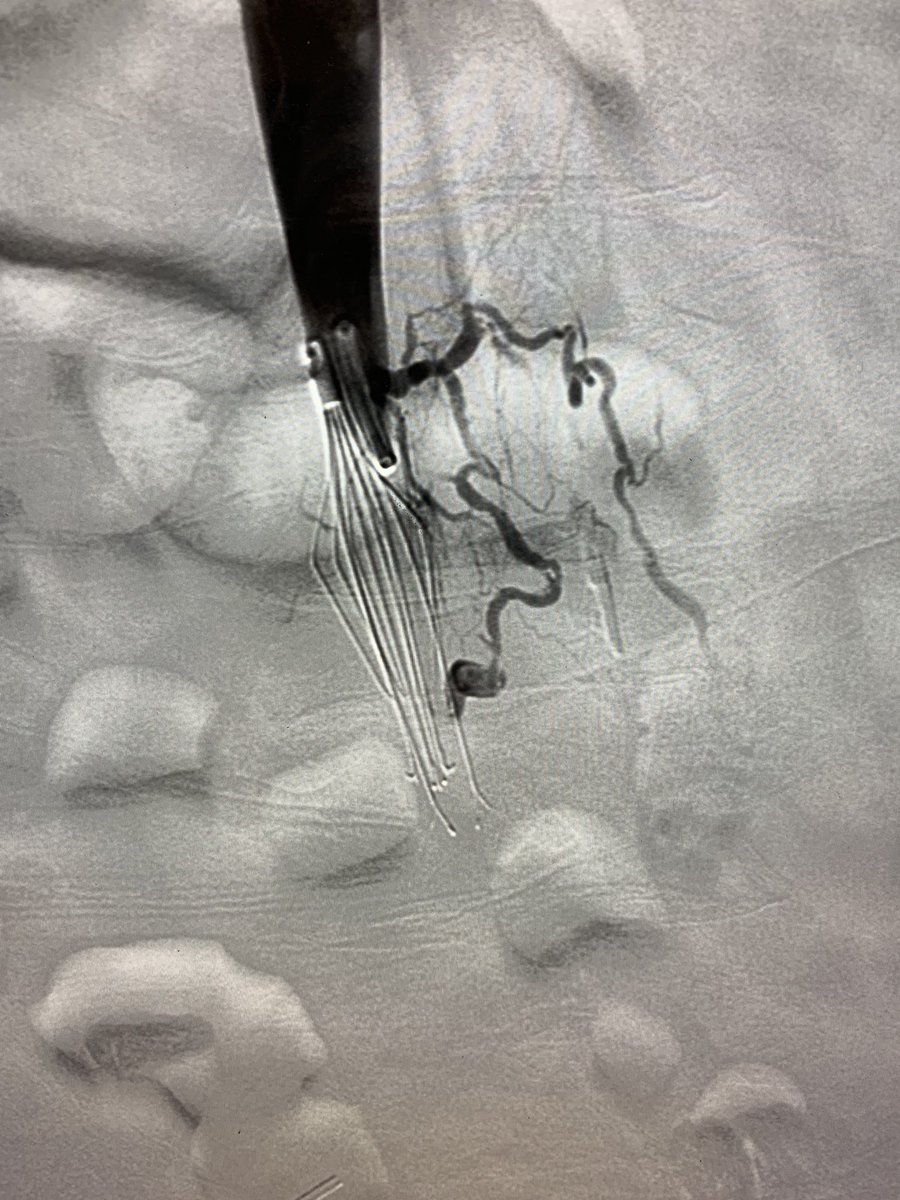

This patient presented with severe leg edema, iliocaval thrombus with 12 year old #IVCfilter. After a night of lysis a large vol of chronic appearing clot persisted. Was able to get most of it out with a few passes with the Inari T20 from popliteal access. #iRad